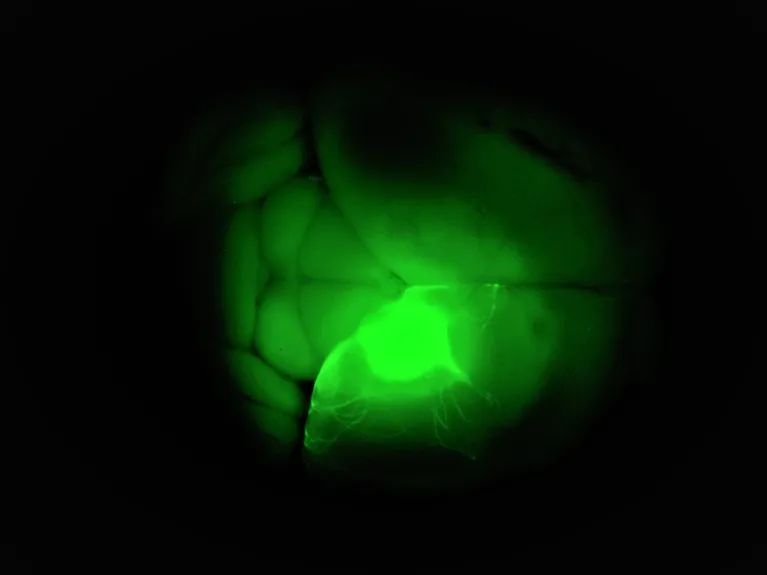

从干细胞制得的人类神经元细胞(绿色)在移植到小鼠大脑内两周后的情况。来源:Pierre Vanderhaeghen